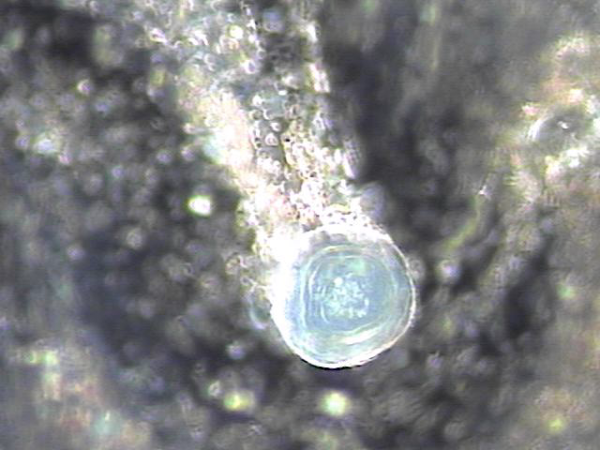

내원 당일 전립선의 표적 치료후 배출된 전립선액의 배양과 PCR 검사를 한후 현미경학적 검사상 치료된 사정관 결석과 전립선의 결석 자료입니다.

On the day of the visit, following targeted prostate treatment, prostatic fluid was discharged and analyzed through culture and PCR testing. Microscopic examination revealed treated ejaculatory duct stones and prostatic calculi.

전립선과 사정관 그리고 사정관입구의 결석 치료중 사정관의 좁은 입구와 전립선관의 막혀 있는 입구로 커다란 결석이 배출시 압력으로 좁아져 있거나

막혀 있던 섬유화된 입구의 손상이 예상되는 현미경학적 사진입니다.

This is a microscopic image taken during the treatment of stones in the prostate, ejaculatory ducts, and the ejaculatory duct orifices.

It shows that large stones being expelled through the narrowed or obstructed fibrotic openings of the ejaculatory and prostatic ducts likely caused mechanical damage due to pressure during expulsion.